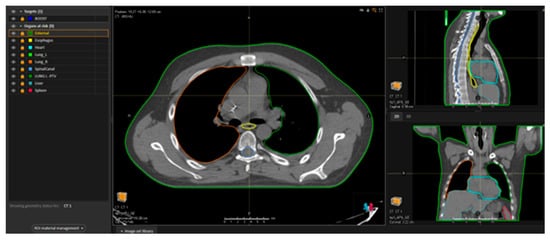

- Loginova, A.A.; Tovmasian, D.A.; Lisovskaya, A.O.; Kobyzeva, D.A.; Maschan, M.A.; Chernyaev, A.P.; Egorov, O.B.; Nechesnyuk, A.V. Optimized Conformal Total Body Irradiation methods with Helical TomoTherapy and Elekta VMAT: Implementation, Imaging, Planning and Dose Delivery for Pediatric Patients. Front. Oncol. 2022, 12, 785917. [Google Scholar] [CrossRef]

- Hoeben, B.A.W.; Saldi, S.; Aristei, C.; Engellau, J.; Ocanto, A.; Hiniker, S.M.; Misson-Yates, S.; Kobyzeva, D.A.; Pazos, M.; George Mikhaeel, N.; et al. Rationale, implementation considerations, delineation and planning target objective recommendations for volumetric modulated arc therapy and helical tomotherapy total body irradiation, total marrow irradiation, total marrow and lymphoid irradiation and total lymphoid irradiation. Radiother. Oncol. J. Eur. Soc. Ther. Radiol. Oncol. 2025, 206, 110822. [Google Scholar] [CrossRef]